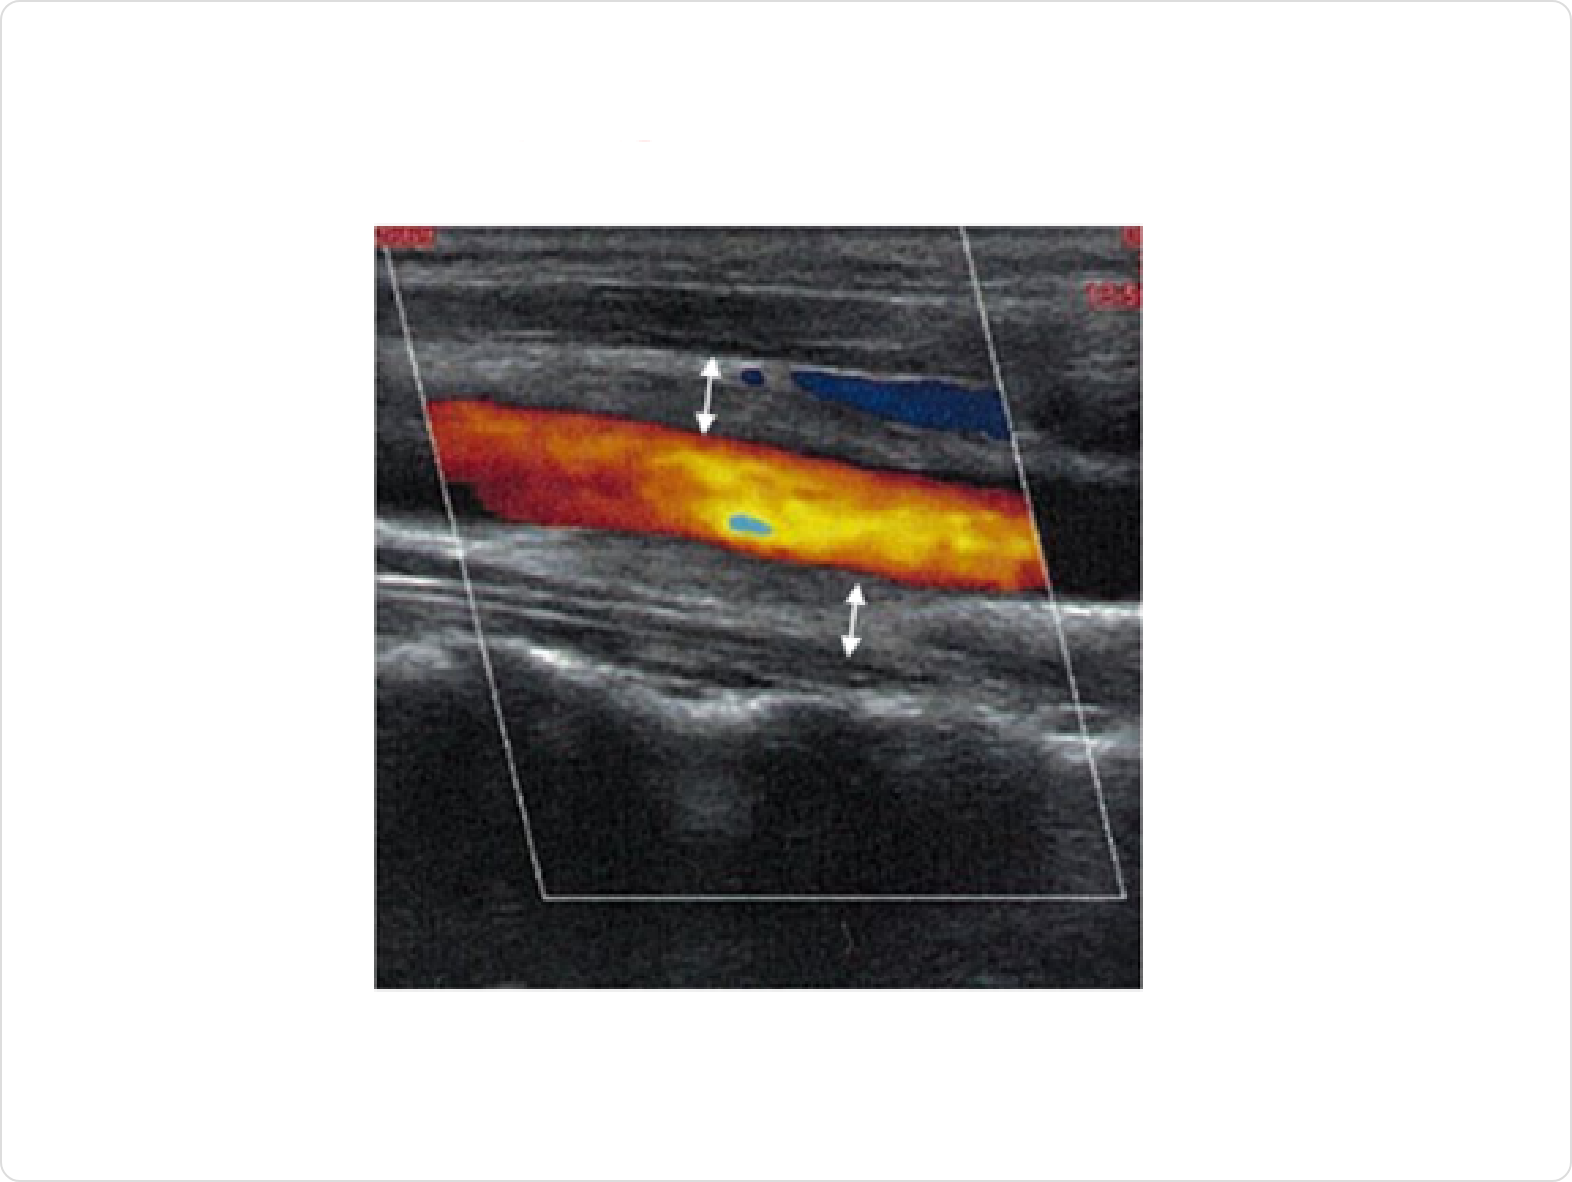

頸動脈エコー

頸動脈エコーは、安全に頸動脈の壁厚を測定できる検査です。下記の画像では赤いところが血液が流れている部分(血管内腔)で、矢印で示す箇所が肥厚した血管壁です。頸部しか検査をすることはできませんが、安全に繰り返し検査をすることが可能です。